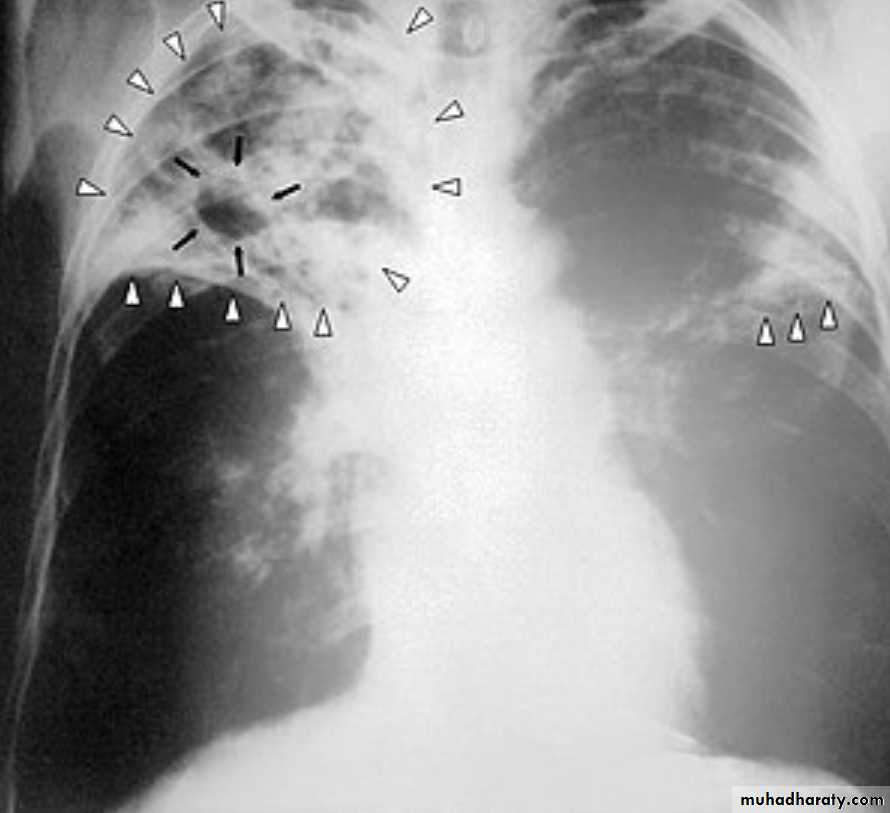

Either occurs as a reinfection by mycobacterium TB or reactivation of primary infection when there is impairment in the immunity of the patient.Grossly: usually occurs at the apex of the lung with minimal lymph node involvement. There is marked damage in the lung parenchyma with cavity formation

Microscopically: Epitheloid granulomas with central necrosis & cavity.

Healing by fibrosis or may spread forming progressive secondary TB